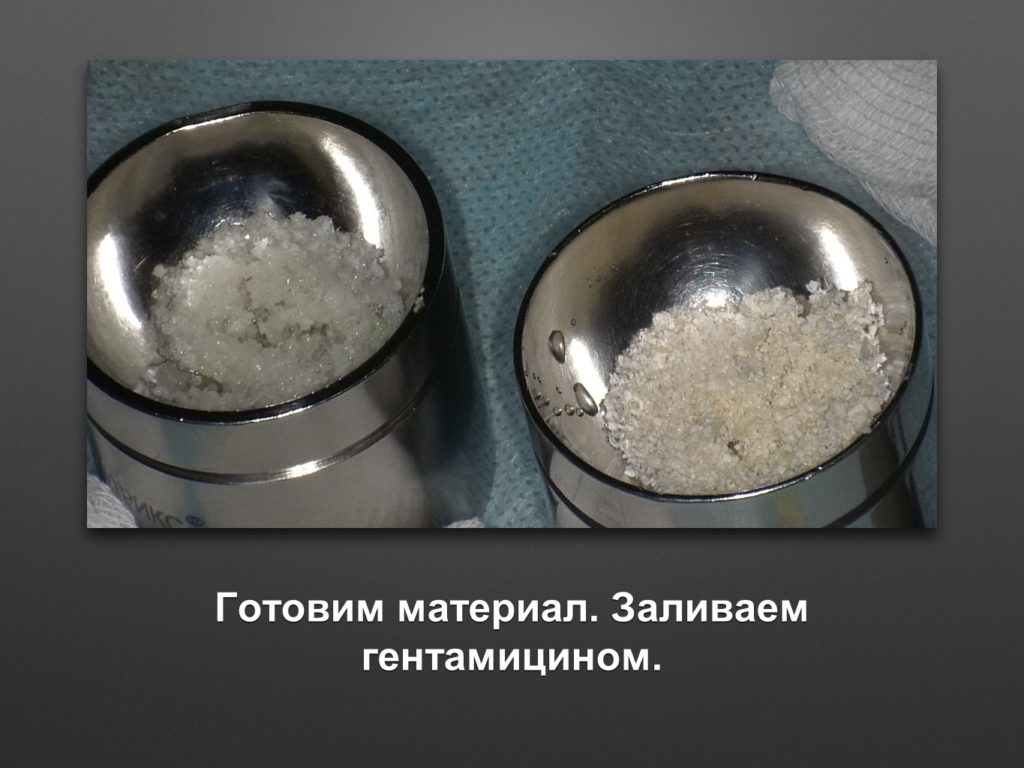

КУПИТЬ ЕМКОСТЬ ДЛЯ ЗАМЕШИВАНИЯ КОСТНОГО МАТЕРИАЛА KOHLER 6739